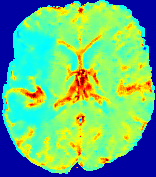

LesionRefer to captionRefer to captionRefer to captionRefer to captionRefer to captionRefer to caption𝐕rgbsubscript𝐕𝑟𝑔𝑏{\bf{V}}_{rgb}Refer to captionRefer to captionRefer to captionRefer to captionRefer to captionRefer to caption𝐕2subscriptnorm𝐕2{\|\bf{V}}\|_{2}Refer to captionRefer to captionRefer to captionRefer to captionRefer to captionRefer to captionRefer to caption3.53.53.52.82.82.82.12.12.11.41.41.40.70.70.70.00.00.0(mm/s)𝑚𝑚𝑠(mm/s)D𝐷DRefer to captionRefer to captionRefer to captionRefer to captionRefer to captionRefer to captionRefer to caption0.0200.0200.0200.0160.0160.0160.0120.0120.0120.0080.0080.0080.0040.0040.0040.0000.0000.000(mm2/s)𝑚superscript𝑚2𝑠(mm^{2}/s)Slice #1Slice #2Slice #3Slice #4Slice #5Slice #6

Figure 4: PIANO feature maps for another patient in the ISLES 2017 training set, where the lesion is located in the right hemisphere. Top row: segmented stroke lesion region (white) on different slices. The corresponding slices for the PIANO feature maps are shown in the following rows.

For a better insight into an estimated velocity field 𝐕𝐕{\bf{V}} and diffusion field 𝐃𝐃{\bf{D}}, we compute the following maps: (1) 𝐕rgbsubscript𝐕𝑟𝑔𝑏{\bf{V}}_{rgb}: Color-coded orientation map of 𝐕=(Vx,Vy,Vz)T𝐕superscriptsuperscript𝑉𝑥superscript𝑉𝑦superscript𝑉𝑧𝑇{\bf{V}}=(V^{x},V^{y},V^{z})^{T}, obtained by normalizing 𝐕𝐕{\bf{V}} to unit length and mapping its 3 components to red, green, blue respectively; (2) 𝐕2subscriptnorm𝐕2\|{\bf{V}}\|_{2}: 222 norm of 𝐕𝐕{\bf{V}}; (3) D𝐷D: scalar field in Eq. 5.

Fig. 3 and Fig. 4 show the PIANO feature maps estimated from two ISLES 2017 patients: all are highly consistent with the lesion in both cases. Details of the blood flow trajectories are revealed in 𝐕rgbsubscript𝐕𝑟𝑔𝑏{\bf{V}}_{rgb} by the ridged patterns and the sharp changes of colors in the unaffected (right) hemisphere, while the flat patterns appearing within the lesion provide little directional information about the velocity and indicate low velocity magnitudes. Velocity magnitudes are more directly visualized via 𝐕2subscriptnorm𝐕2\|{\bf{V}}\|_{2}, from which one can easily locate the lesion where 𝐕2subscriptnorm𝐕2\|{\bf{V}}\|_{2} is low. D𝐷D also indicates lower diffusion values in the lesion, though with less contrast potentially due to the fact that it captures the accumulated effect of CA diffusion at the voxel-level.